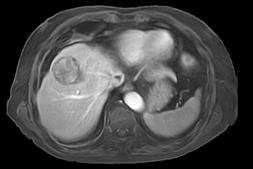

With 4D FreeBreathing, you can now offer free-breathing MRI liver to a broader population, while improving imaging confidence and the patient experience. This allows you to address patients who have difficulty holding their breath or find it difficult to follow breathing instructions.

4D FreeBreathing – Dynamic 3D T1w TFE Resolution: 1.6 X 1.6 X 5.0 mm Scan time: 3:16min Magnet ic Resonance